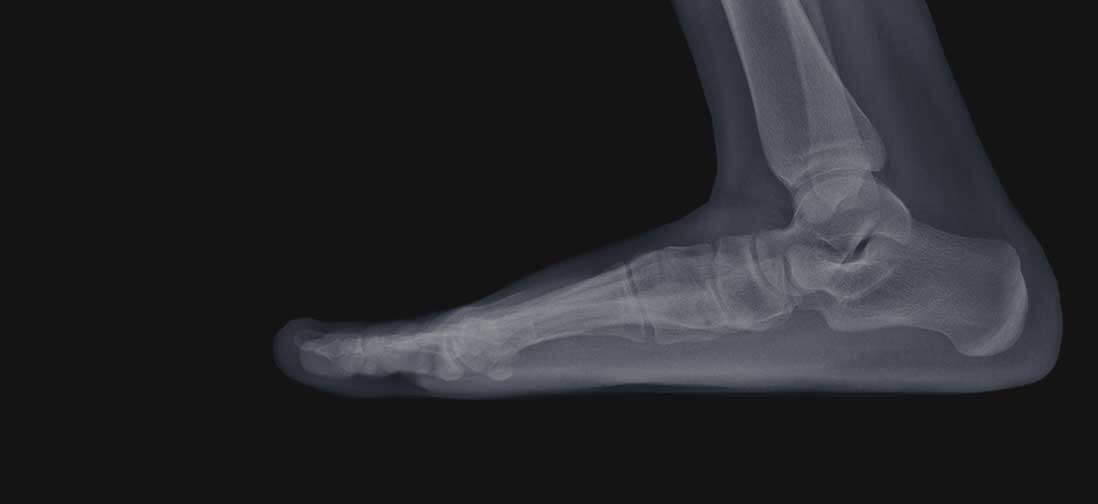

Is a foot or ankle condition forcing you to change your routine? Whether you're doing less due to discomfort or are too embarrassed to take off your shoes and socks, dealing with a painful or unsightly podiatric problem can make it difficult to live your best life. Fortunately, you don't have to take this lying down. At Omaha Foot and Ankle Specialists, we can help you stand up to pain and get back to the activities you enjoy.

Since 1991, our premier podiatry practice has helped countless patients overcome ailments preventing their feet from looking and feeling their best. Our highly skilled podiatrists, Dr. Michael Cullen and Dr. Nathan Penney, provide compassionate and comprehensive care for all manner of foot and ankle issues from ingrown toenails to ankle replacements and everything in between. Most importantly, we provide the information, education, and support you need to feel confident in your care.

Have a bunion or hammertoe that's making every step miserable? Sports injury got you sitting on the sidelines? Need a gait assessment or guidance for achieving your athletic goals safely? Your feet and ankles are in good hands. Schedule an appointment to find out what we can do for you.